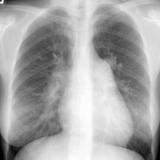

ASD 1 PA

Date: 03/17/2004

Views: 2762